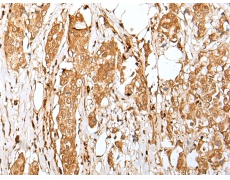

IHC positive control: |

Human tonsil and human breast cancer |